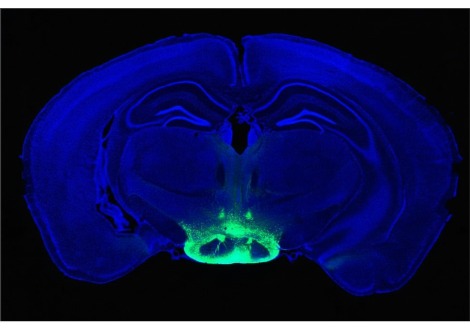

توصّل "جيفري ديفز" وفريقه من جامعة سوانسي في المملكة المتحدة إلى دليل آخر على تحفيز الجريلين لخلايا الدماغ على الانقسام والازدياد في عمليّة تدعى "تكوين الخلايا العصبية".

عندما إضافة الهرمون لخلايا دماغ الفأر تحولت لجين معروف بقدرته على استهداف تكوين الخلايا العصبية والذي يطلق عليه "عامل نمو الخلايا الليفية".